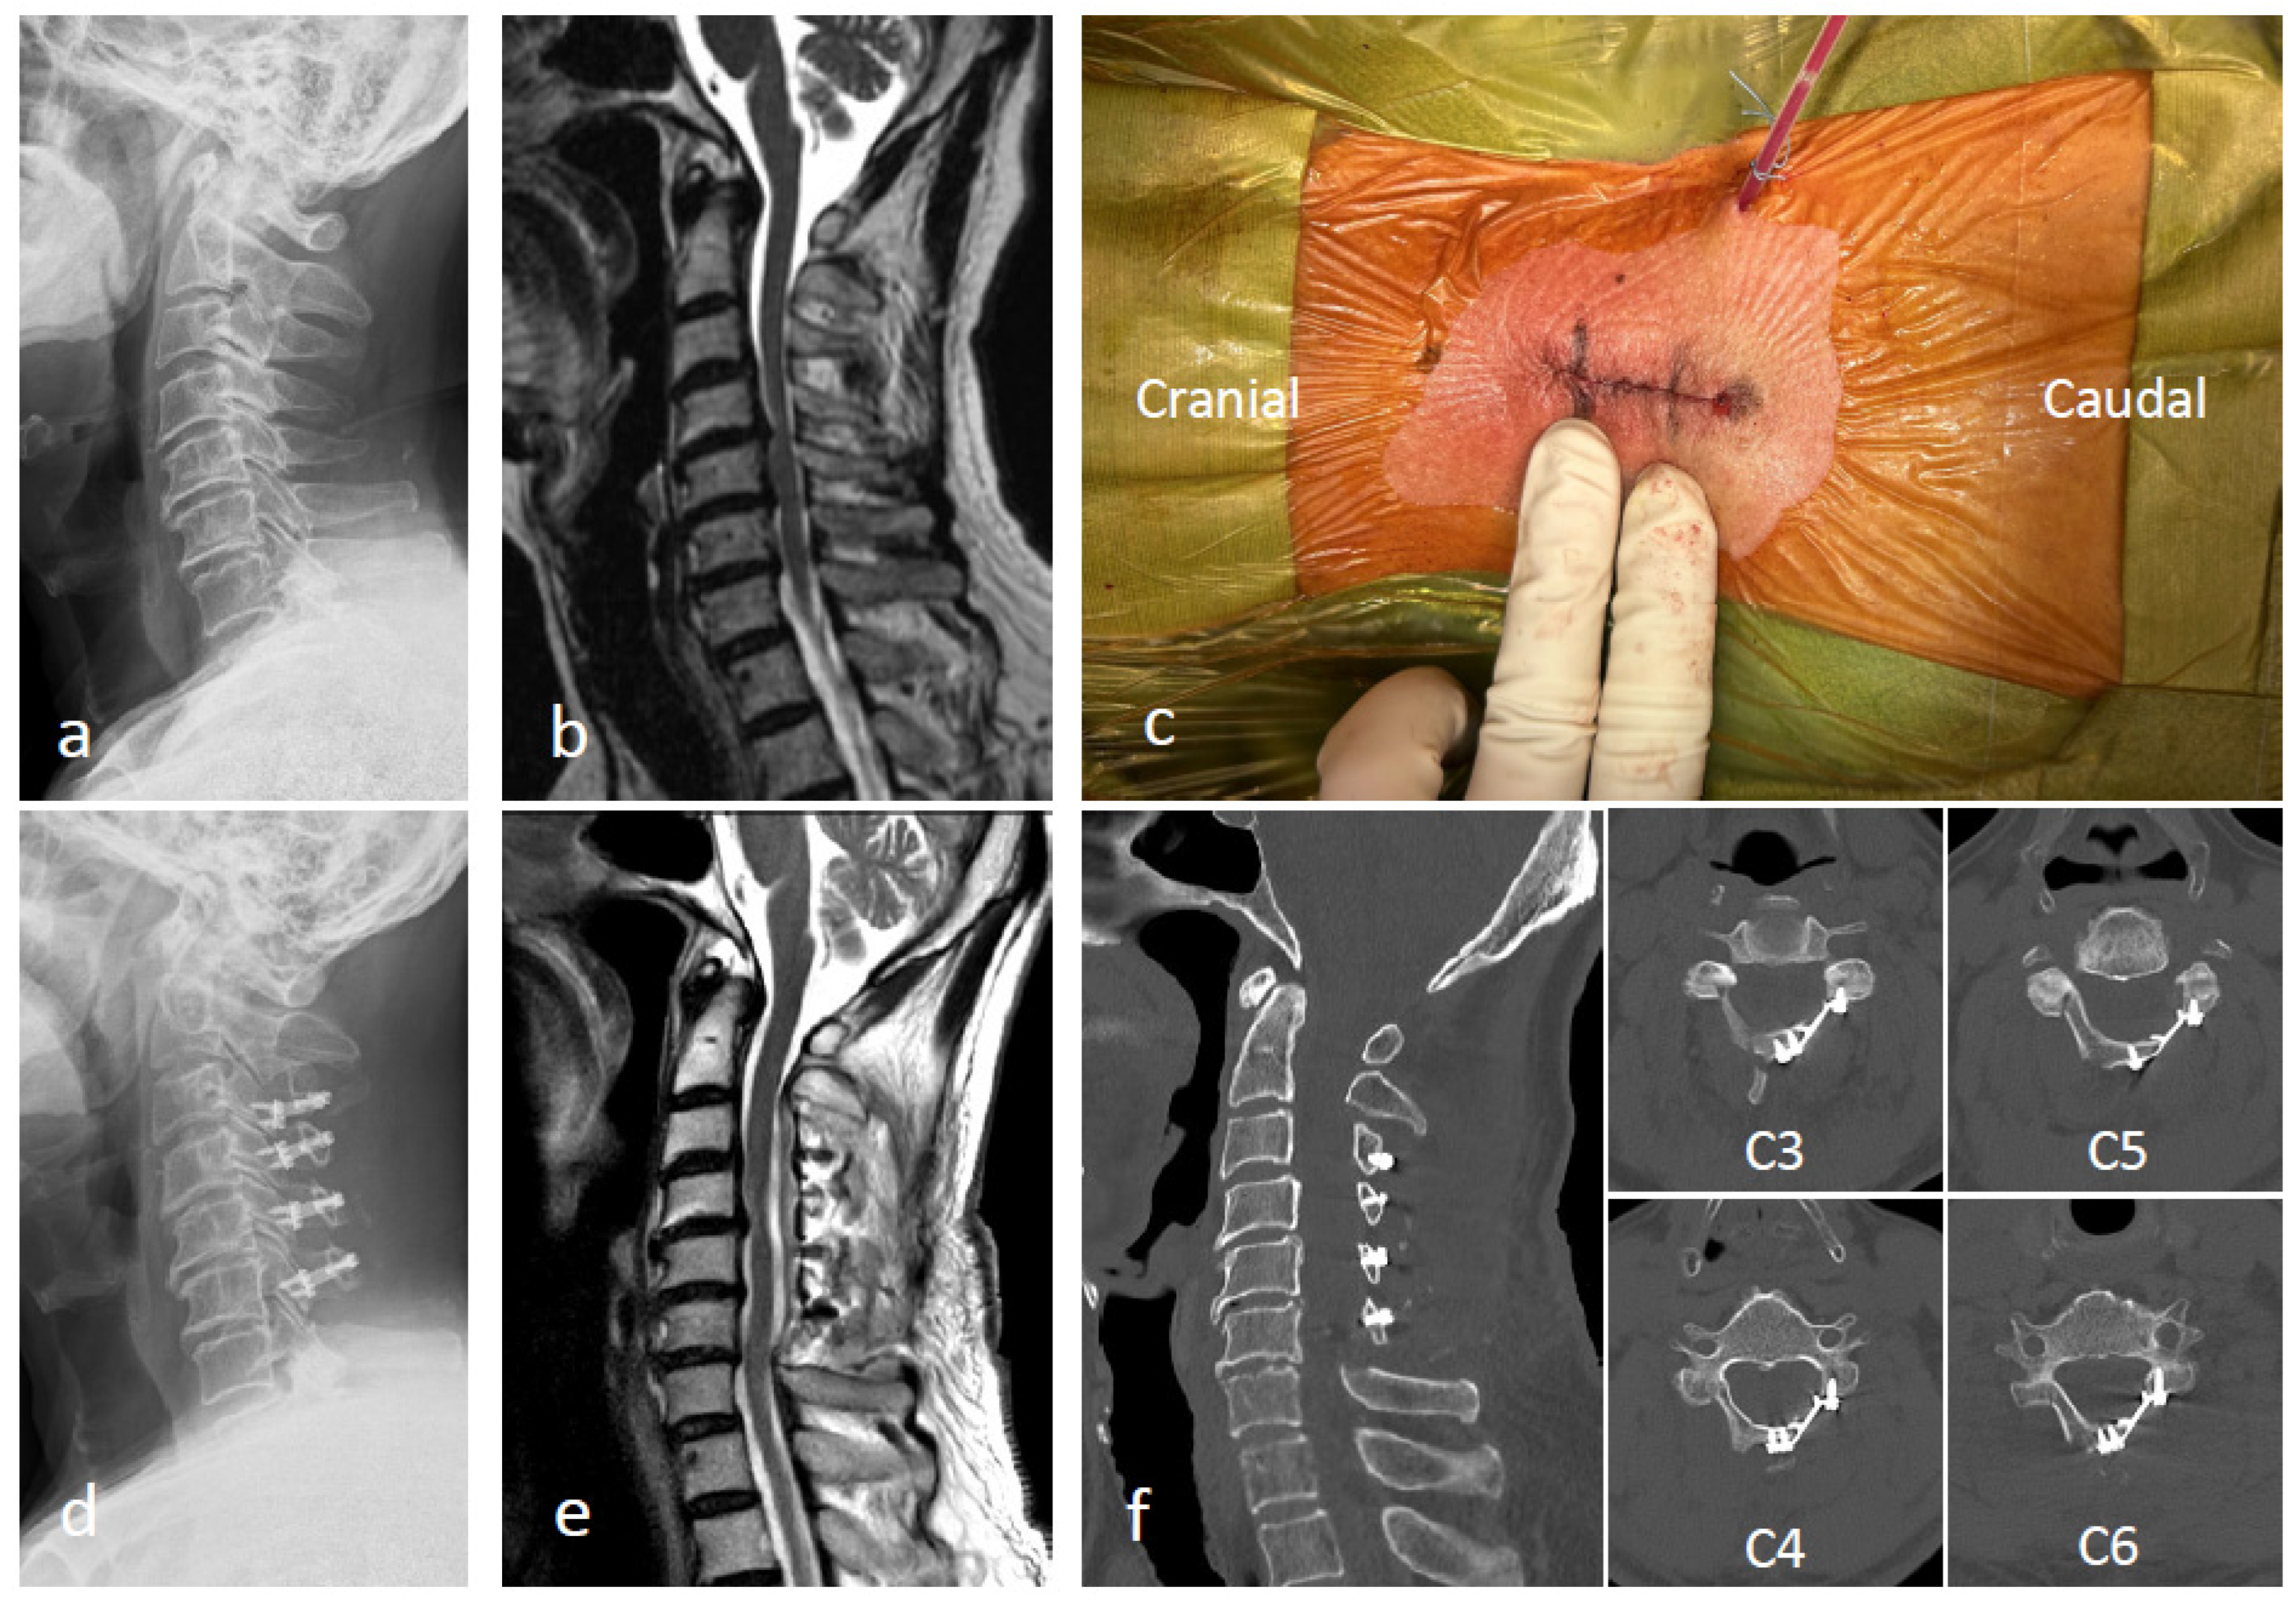

Representative Case